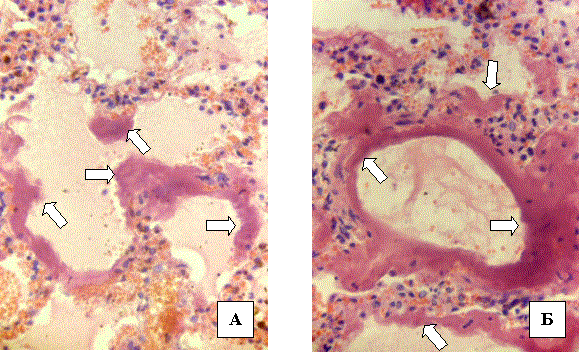

Проявами,

які патогномонічні для гРДС, є наступні: розширення альвеолярних ходів при

колапсі решти паренхіми; альвеолярні мішечки або колабовані, або навпаки - розширені

ексудатом; поширена денудація (оголення епітеліальної поверхні) альвеолярних

ходів та альвеолярних мішечків (поширений некроз альвеолоцитів І-го типу);

присутні так звані «гіалінові мембрани» (Рис.2), які найбільш виражені впродовж

альвеолярних ходів (Рис.2 А), звідки вони переходять на стінку альвеол і

поширюються через альвеолярні пори. Іноді гіалінові мембрани повністю вкривають

денудовану поверхню респіраторних відділів (Рис.2 Б).

Рис.2. Гострий респіраторний

дистрес-синдром, ексудативна фаза. Мікроскопічна картина. Патологоанатомічне

дослідження. Гіалінові мембрани вказані стрілками. Гематоксилін і еозин. Об.20х.

Ок.10х.